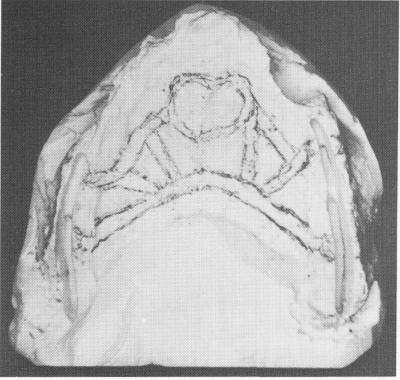

Fig. 11-189. An implant was designed on the master stone model and the grooves deepened according to the x-ray findings.

1 Completed casting over maxillary stone model